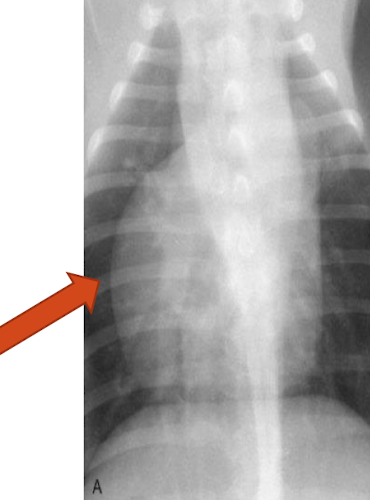

What is the arrow pointing to?

large osteophyte on the anconeal process (earliest change seen in DJD)